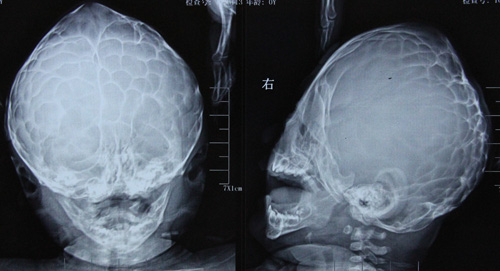

颅缝早闭症的影像学特点

颅缝早闭症的影像学检查主要有X 线、CT、MRI 和超声检查,其中平片具有重要诊断价值。X 线片的影像特点:X 线检查主要用于颅骨受压情况和颅面畸形的筛查,明确骨骼畸形以及相应的软组织改变。如有颅压高者,则需手术解除颅骨压迫,一般预后较好;颅压不高者,则要考虑由脑发育不全引起的继发性颅缝早闭症,预后较差且可能会留有后遗症。尖头和短头畸形可见颅底下陷等表现。CT 影像特点:CT 检查可以明确颅骨颅缝的一般情况,平扫可了解颅骨的完整性及部分颅顶缝,如人字缝、冠状缝、额缝。矢状面、冠状面扫描可以了解矢状缝情况。国外学者对CT 三维重建成像的研究较多,如新型软件进行分析,得出前斜头畸形CT 三维重建颅盖的四种图形,有利于手术矫正。Glasgow 等对前斜头畸形进行研究,使用对角颅经差来定量斜头畸形,为治疗提供依据。Losee 等对非骨性融合的后斜头和骨性融合斜头进行了对比研究,发现骨性融合斜头畸形的枕骨是不规则四边形,并得出人字缝融合不是骨性融合斜头畸形唯一的放射学特征。MRI 影像学特点:MRI 检查主要了解脑发育情况及颅骨生长情况,对判断颅内继发改变如脑积水的程度及梗阻部位以及与其他颅脑发育畸形相鉴别具有重要意义。